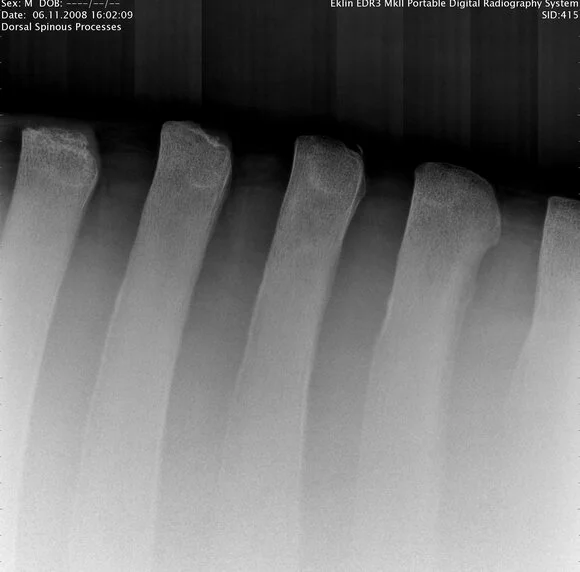

Back Radiographs:

The vertical portion of the vertebrae should be evenly spaced as is seen with this normal radiograph of a horse's spine. Compare this with the one to the right that was taken in the saddle region.

As you will see in this radiograph versus the one to the left, the vertebrae are touching or rubbing against one another. This x-ray was taken without the weight of a rider. Once there is weight on the horse's back the problem would be significantly worsened. This is called "Kissing Spine" syndrome.